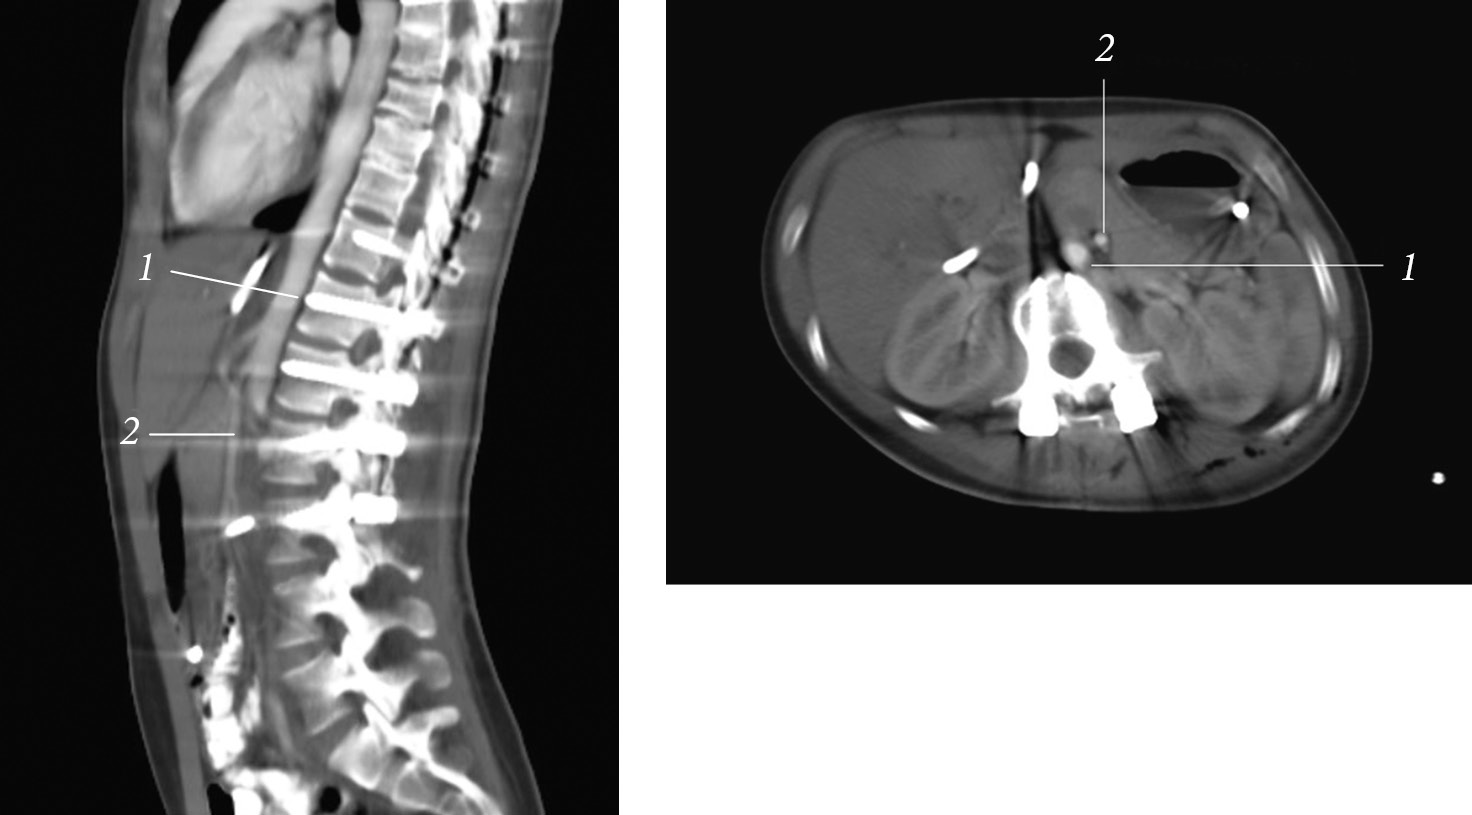

Radiographs, multispiral computed tomography (MSCT) of the spine revealed radiation pattern of severe idiopathic scoliosis of the thoracic spine. The left-sided scoliotic arch Th6–Th12 of 75° according to Cobb was determined. In functional images, the scoliotic arch was rigid, corrected to a value of 70° according to Cobb. The frontal balance was physiological. Rotation and torsion of the vertebrae have secondary degenerative and dystrophic changes in the vertebral-motor segments of the thoracic and lumbar regions (most pronounced at the apices of the scoliotic arches). No areas of bone density were revealed in the spinal canal (Fig. 1, 2).

Fig. 1. X-ray of the spine in a frontal view in a standing position

A combined MSCT with contrasting of the gastrointestinal tract and angiography of the abdominal cavity vessels was performed (Fig. 6). In specific, a tube was installed to the level of the duodenum, without distal disturbances in the contrast agent passage. Contrast agent traces in the small and large intestine were found. The stomach was not enlarged, the gas bubble was 110 × 40 mm, and the contents were traces of fluid. When contrasting of the vessels, the aortic–mesenteric angle was 7.7° (normal is 25°–60°), and the aortic–mesenteric distance was 5.1 mm (normal is 10–28 mm), which is a sign of SMA syndrome.

Fig. 6. Combined multispiral computed tomography with contrasting of the gastrointestinal tract and angiography of the vessels of the abdominal cavity: 1 — aorta; 2 — superior mesenteric artery